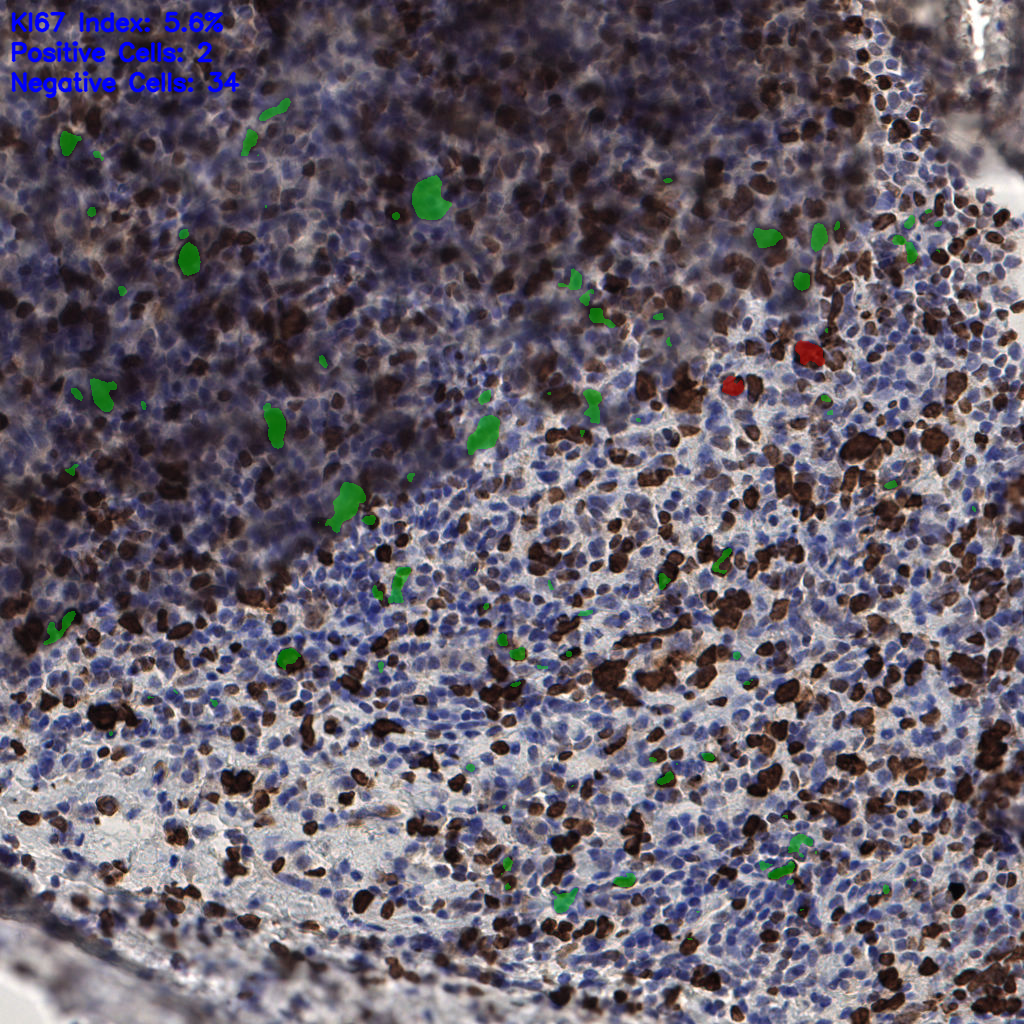

7.85%

Ki67 指数

阴 1104

阳 94

切片统计

总切片

1953

有效

288

已标记

有效率

15%

标记后

标记前